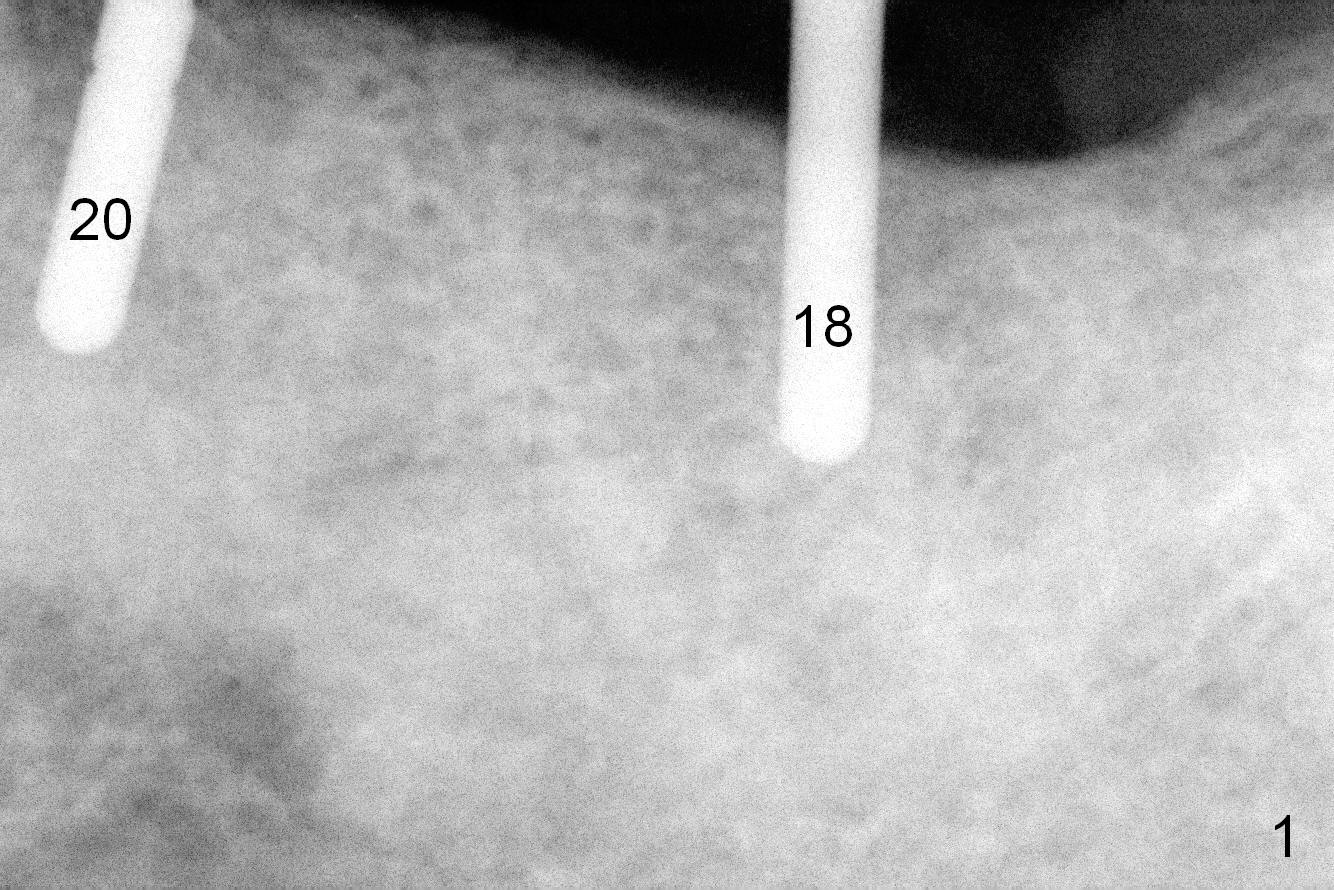

The sites of osteotomies at #18 and 20 are decided by the surgical stent (Fig.1). A 4x14 mm implant is placed at the site of #20 (Fig.2), and a 5x14 mm one at #18 (Fig.3) with primary stability. When 3 mm long abutments are placed for an immediate provisional (Fig.4 A), there is no or limited clearance with the opposing dentition (Fig.5). In spite of the fact that the implants are placed deeper, the abutments and the opposing supraerupted teeth #13 and 15 (Fig.5 arrows) have to be reduced. Finally the abutment at #18 has to be removed. No provisional is fabricated. Periodontal dressing is applied around the abutment at #20 and the adjacent teeth. It appears that the tissue-level implant is not suitable for the 2nd molar with limited vertical clearance.

There is bone loss at #18 3.5 months postop with mild purulent discharge from the gingival sulcus (1 month post healing cuff placement, Fig.6). After heavy abutment and the tooth #15 reduction, the provisional FPD has to be made to increase vertical height.